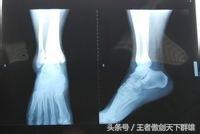

第一步,如果崴到脚,脚踝立刻就肿胀,而且很痛,建议首先到医院拍张片子看一下有没有伤到骨头。

如果是伤到骨头,要听从医生的进行治疗。

如果没有伤到骨头,就可以在家进行下面的处理了。